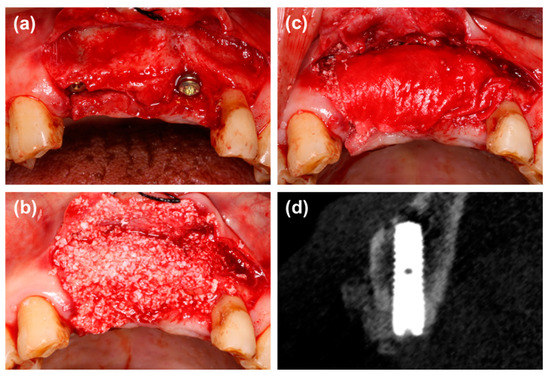

2.2. Surgical Procedures

2.3. CBCT Analysis